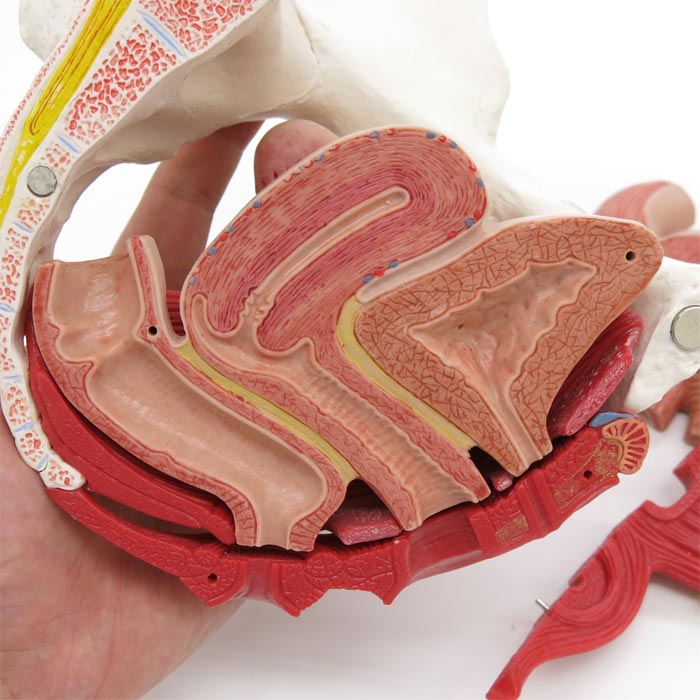

Pelvic Floor Muscles Stock Illustration

H10 女性骨盤内臓器 2分解モデル Medimann メディマン タカチホメディカル株式会社

女性骨盤内臓器 2分解モデル ボード型 日本スリービー サイエンティフィック

女性骨盤 内臓 骨盤底筋付 6分解モデル 日本スリービー サイエンティフィック

女性骨盤 内臓 骨盤底筋付 6分解モデル 日本スリービー サイエンティフィック